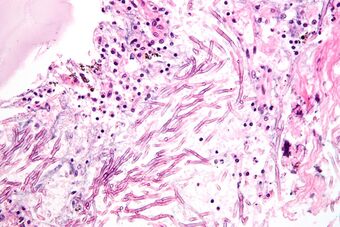

| H&E stain showing a fungal pneumonia (pulmonary aspergillosis) |